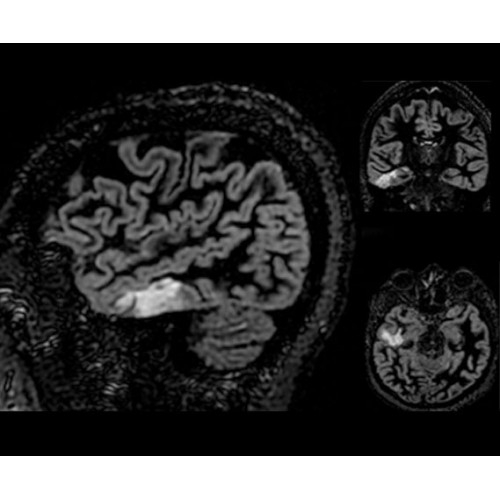

• NeuroWorks — универсальное решение для визуализации анатомии головного мозга, позвоночника, сосудов и периферических нервов с четкой дифференциацией тканей.

Теперь возможности МРТ поражают еще больше благодаря ультрасовременным решениям для визуализации с SIGNA Architect 3.0 Тл, объединяющей новейшие достижения в области МР-технологий и интуитивно понятный интерфейс. Система SIGNA Architect, разработанная на базе новой платформы SIGNA Works, представляет собой гармоничное сочетание дизайна и функциональности. Каждый элемент системы направлен на повышение производительности, эффективности клинической практики, финансовых показателей, а также комфорта и безопасности пациента.

Поле обзора 50x50x50 см и апертура шириной 70 см позволят достоверно визуализировать сложные анатомические области для пациентов с крупным телосложением, например, плечи и бедра. Феноменальная однородность системы SIGNA Architect обеспечивает наиболее широкое поле обзора с улучшенными характеристиками градиентов. Ничто не останется незамеченным.